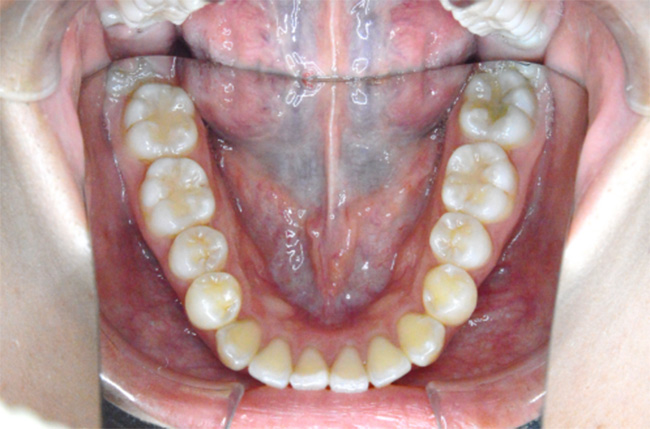

治療開始時